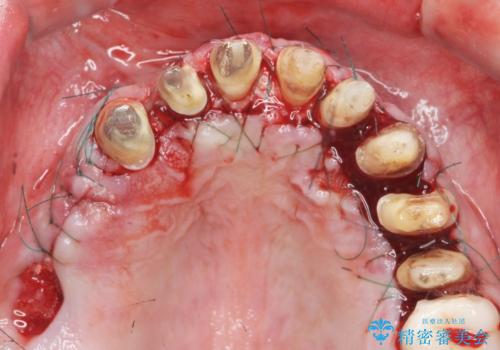

歯周外科を行い歯と歯槽骨・歯肉の関係を是正することで歯ぐきの状態を改善し、将来に亘り安定した歯周環境の維持を期待できるセラミック治療を実践します。

歯ぐきが腫れたままの状態だと、違和感が生じるとともに常に炎症が存在する環境となってしまうので非常に好ましくない口腔内環境です。

- 外科手術のため、術後に出血、痛みや腫れ、違和感を伴います